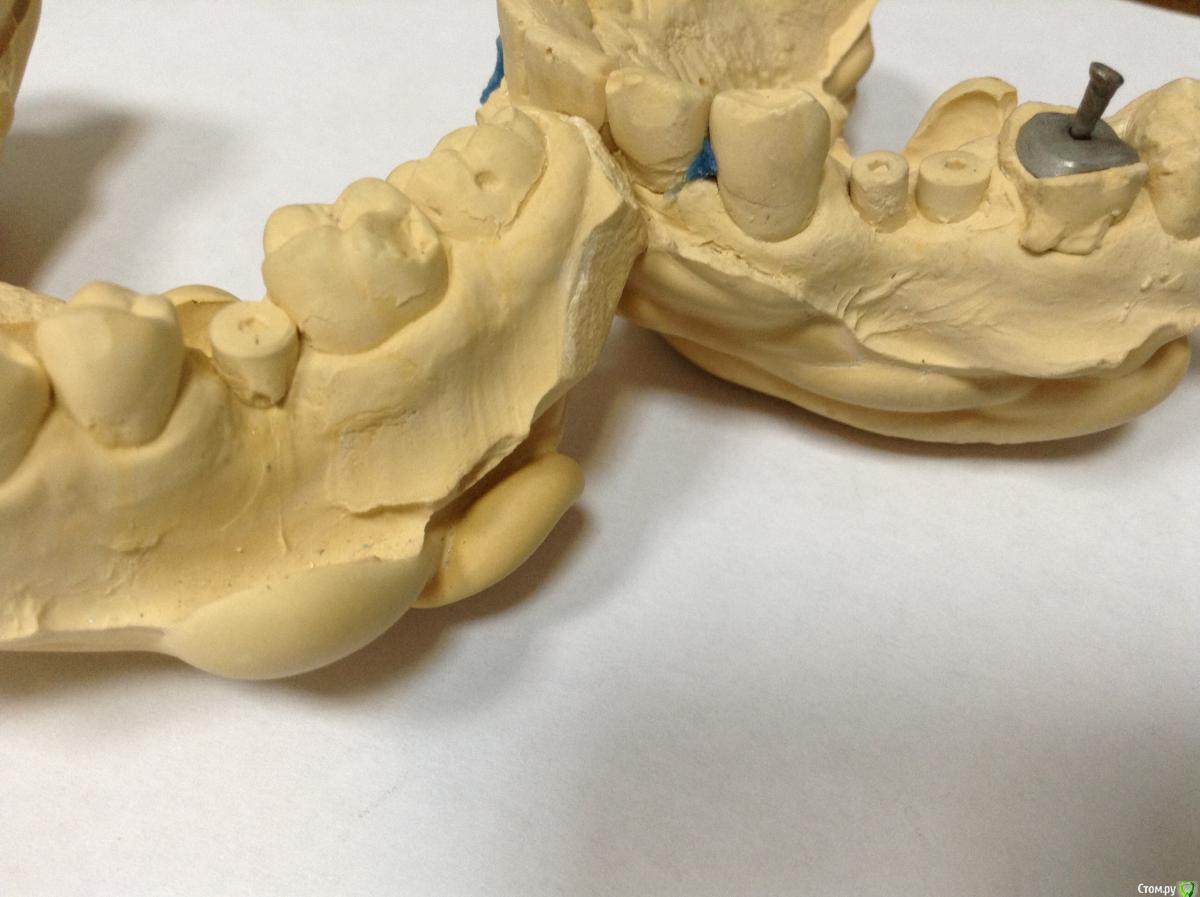

ksenistom Опубликовано 2 декабря, 2014 Поделиться Опубликовано 2 декабря, 2014 Уважаемые коллеги,подскажите пожалуйста,как быть в данной клинической ситуации? Ссылка на комментарий

Aquarius Опубликовано 2 декабря, 2014 Поделиться Опубликовано 2 декабря, 2014 Почему места недостаточно?)) Все получится, даже у среднеграмотного техника. Где одиночка, премолярчик выйдет) Ссылка на комментарий

ksenistom Опубликовано 2 декабря, 2014 Автор Поделиться Опубликовано 2 декабря, 2014 Почему места недостаточно?)) Все получится, даже у среднеграмотного техника. Где одиночка, премолярчик выйдет)Мне хирург так и сказал,только что мне с 6 делать?там все вплотную,расстояние должно 1,5мм минимум быть? Ссылка на комментарий

chernov Опубликовано 2 декабря, 2014 Поделиться Опубликовано 2 декабря, 2014 Мне хирург так и сказал,только что мне с 6 делать?там все вплотную,расстояние должно 1,5мм минимум быть?от чего-до чего,расстояние должно быть?знаете? Ссылка на комментарий

ksenistom Опубликовано 2 декабря, 2014 Автор Поделиться Опубликовано 2 декабря, 2014 от чего-до чего,расстояние должно быть?знаете?От зуба до импланта 1,5мм,между имплантатами 3мм или я ошибаюсь? Ссылка на комментарий

chernov Опубликовано 2 декабря, 2014 Поделиться Опубликовано 2 декабря, 2014 От зуба до импланта 1,5мм,между имплантатами 3мм или я ошибаюсь?1,5мм ширина костной перегородки для формирования сосочка,а конструктивно(для техника) разницы нет. Ссылка на комментарий

ksenistom Опубликовано 2 декабря, 2014 Автор Поделиться Опубликовано 2 декабря, 2014 1,5мм ширина костной перегородки для формирования сосочка,а конструктивно(для техника) разницы нет.То есть в данной ситуации достаточно места для протезирования? Ссылка на комментарий

chernov Опубликовано 2 декабря, 2014 Поделиться Опубликовано 2 декабря, 2014 (изменено) То есть в данной ситуации достаточно места для протезирования?в технической части-да,достаточно,а с эстетикой могут возникнуть проблемы. Изменено 2 декабря, 2014 пользователем chernov Ссылка на комментарий

togrul Опубликовано 2 декабря, 2014 Поделиться Опубликовано 2 декабря, 2014 В данной ситуации лучше сделать на стандартных абатментах , места мало между имплантатами гигиена будет страдать. Ссылка на комментарий

Евгений Ходыкин Опубликовано 3 декабря, 2014 Поделиться Опубликовано 3 декабря, 2014 Делайте в блоке премоляры, техники размоделировать смогут. Про эстетику забыть... Ссылка на комментарий

ksenistom Опубликовано 3 декабря, 2014 Автор Поделиться Опубликовано 3 декабря, 2014 Делайте в блоке премоляры, техники размоделировать смогут. Про эстетику забыть...Премоляры я поняла,что в блоке,спасибо))а что делать с одиночкой? Ссылка на комментарий

chernov Опубликовано 4 декабря, 2014 Поделиться Опубликовано 4 декабря, 2014 одиночку! 1 Ссылка на комментарий

Евгений Ходыкин Опубликовано 4 декабря, 2014 Поделиться Опубликовано 4 декабря, 2014 Премоляры я поняла,что в блоке,спасибо))а что делать с одиночкой?Не ахти какую, но делайте)) Ссылка на комментарий